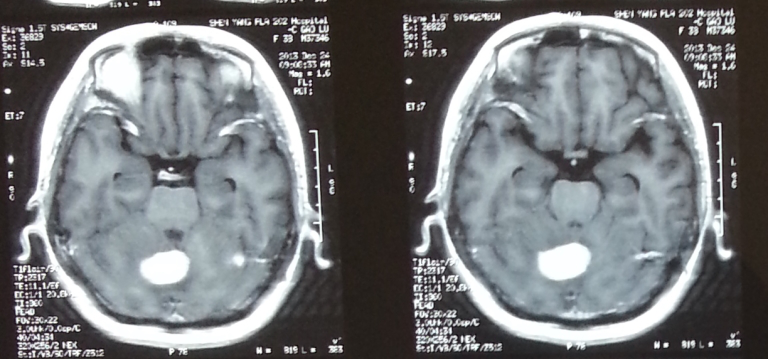

患者高某 女 38岁 乳腺导管癌化疗后脑转移

治疗前

治疗后10个月后复查,肿瘤已经消失